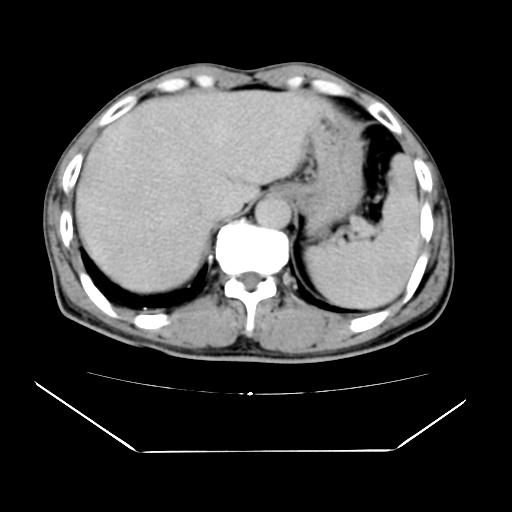

男性,55岁,外院体检afp明显升高,但b超未发现异常,否认乙肝病史。来我院ct增强。有延时扫描。

肝脏右叶动脉期可见低密度影,至延迟期被充填,考虑血管瘤可能性大。

标题: 肝右叶病灶强化

肝右叶病灶

不排除肝右叶肝癌可能。

这个不是肝右静脉吗,这么大的病灶b超不可能发现不了吧

如果这个是癌灶的话则下腔静脉有瘤栓可能

肝6段血管瘤

血管瘤可能性大。

是肝右静脉吧

考虑肝右静脉影。